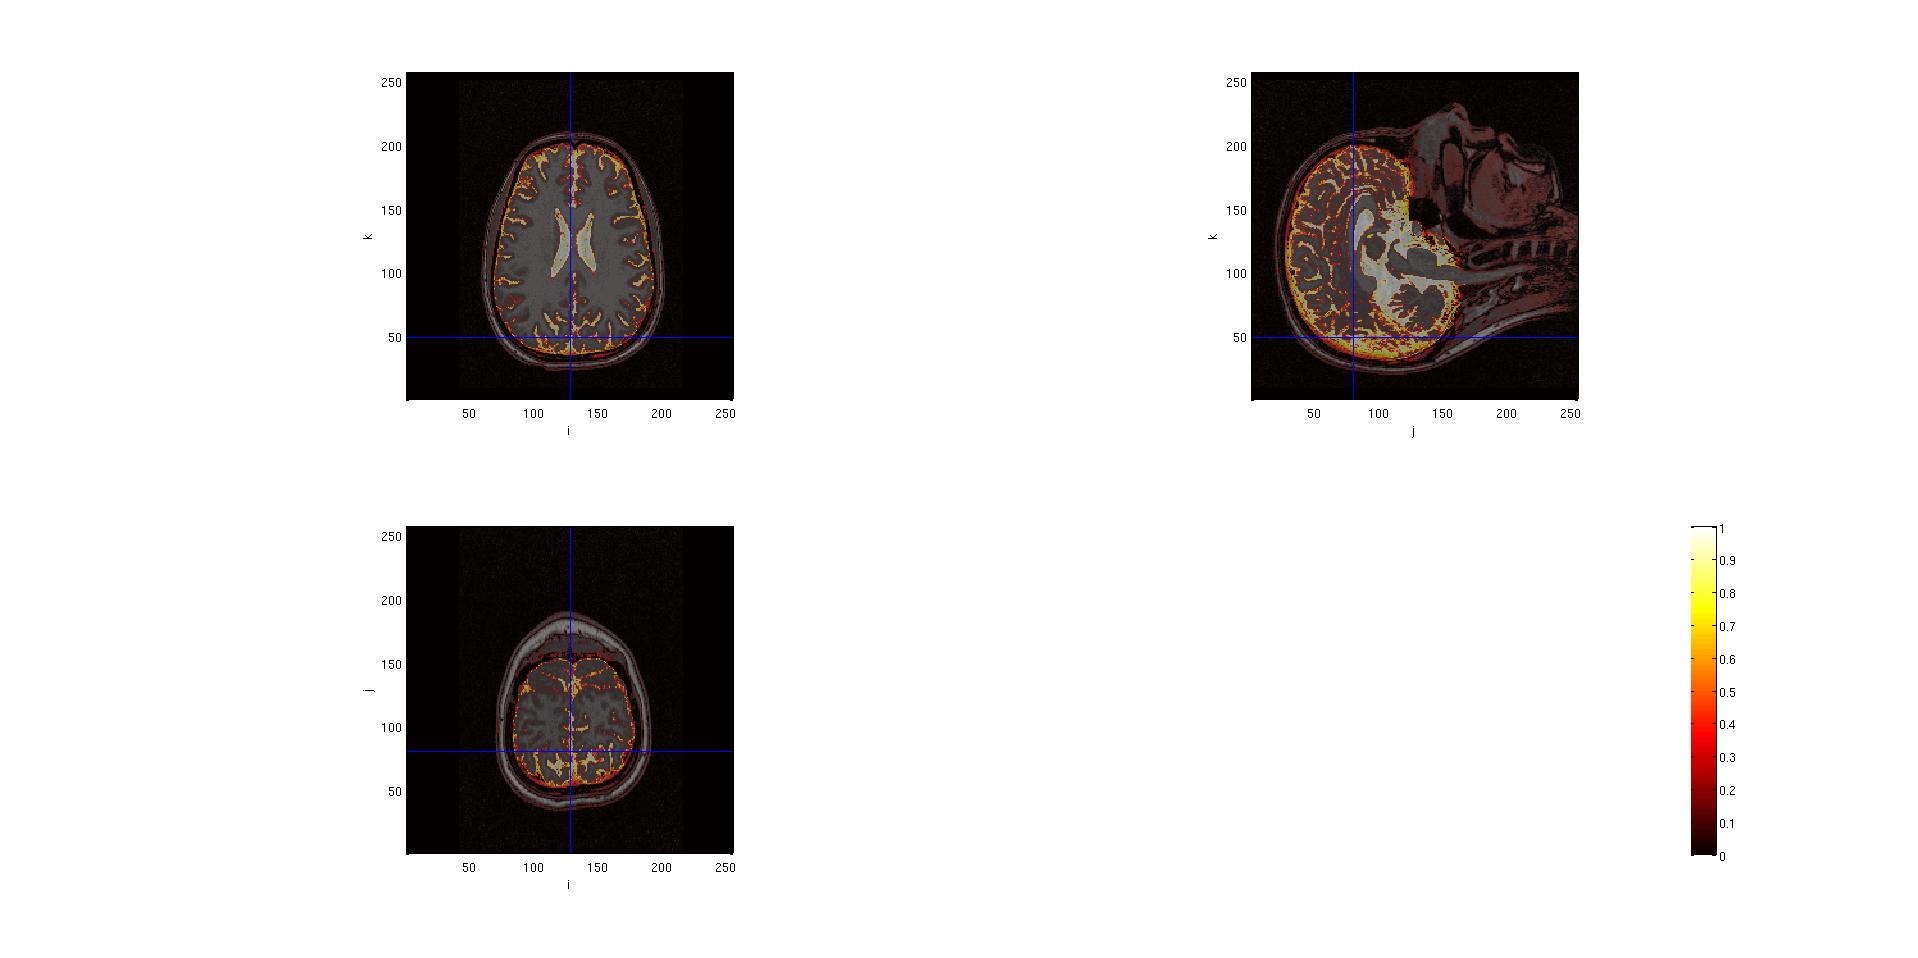

With this kind of segmentation, the output is the identification of the gray matter, the white matter and the cerebro-spinal fluid on the images. It is possible to look at the results of this segmentation.

seg.anatomy = mri.anatomy;

cfg = [];

cfg.funparameter = 'gray';

%or

%cfg.funparameter = 'white';

%cfg.funparamter = 'csf';

cfg.interactive = 'yes'; %(this allows to click on the images in order to see other slices

ft_sourceplot(cfg, seg);

Here are the outputs of ft_volumesegment on data from a .mgz volume, plotted with ft_sourceplot.

seg.csf